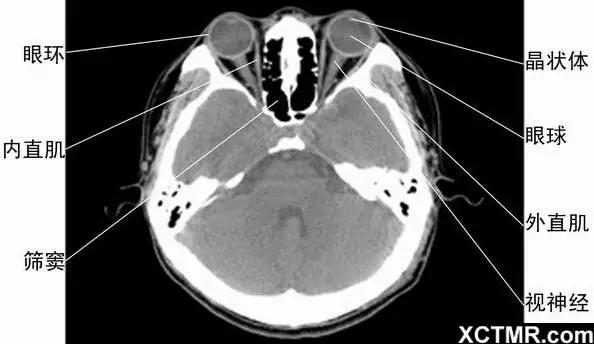

5眼眶橫斷面-CT - 解剖圖片